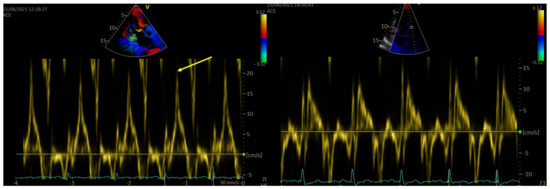

2.3. Echocardiography

- Muthukumar, L.; Rahman, F.; Jan, M.F.; Shaikh, A.; Kalvin, L.; Dhala, A.; Jahangir, A.; Tajik, A.J. The Pickelhaube sign. Novel Echocardiographic Risk Marker for Malignant Mitral Valve Prolapse. JACC Cardiovasc. Imaging 2017, 10, 1078–1079. [Google Scholar] [CrossRef] [PubMed]

- Lauretta, L.; Casalino, G.; Amzulescu, M.; David-Cojocariu, A.; Unger, P. How to improve tissue Doppler imaging sensitivity to detect the Pickelhaube sign. Eur. Heart J. Cardiovasc. Imaging 2020, 21, 746. [Google Scholar] [CrossRef]

| S′ lat (cm/s) | 12 (8–18) | 8 (7–9) | <0.000 | 16 (12–22) | 8 (7–10) | <0.000 | <0.000 | 0.064 |

| Pickelhaube sign, n (%) | 30 (42%) | - | - | 30 (64%) | - | - | - | - |